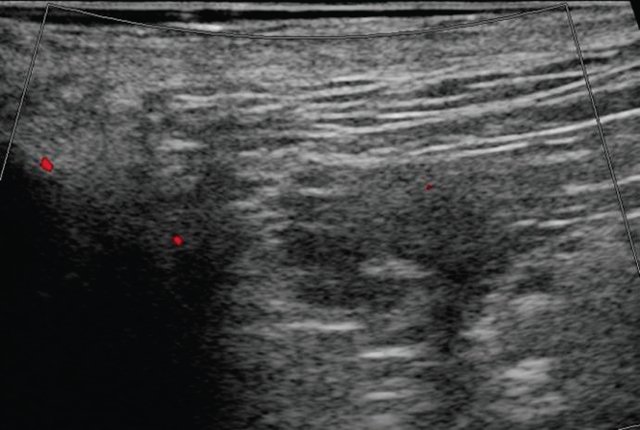

При контрольном УЗ-исследовании: описываемое ранее жидкостное образование в подкожно-жировой клетчатке четко не визуализируется, в его проекции - умеренная неоднородность ткани без четких очаговых изменений (рис. 4, а). Сосудистый рисунок в подкожно-жировой клетчатке в данной проекции не обогащен (рис. 4, б).

а) В-режим. Описываемое ранее жидкостное образование со свищевым ходом в подкожно-жировой клетчатке четко не визуализируется, в его проекции - умеренная неоднородность ткани без четких очаговых изменений.

б) Режим ЦДК. Сосудистый рисунок в подкожно-жировой клетчатке в данной проекции не обогащен.